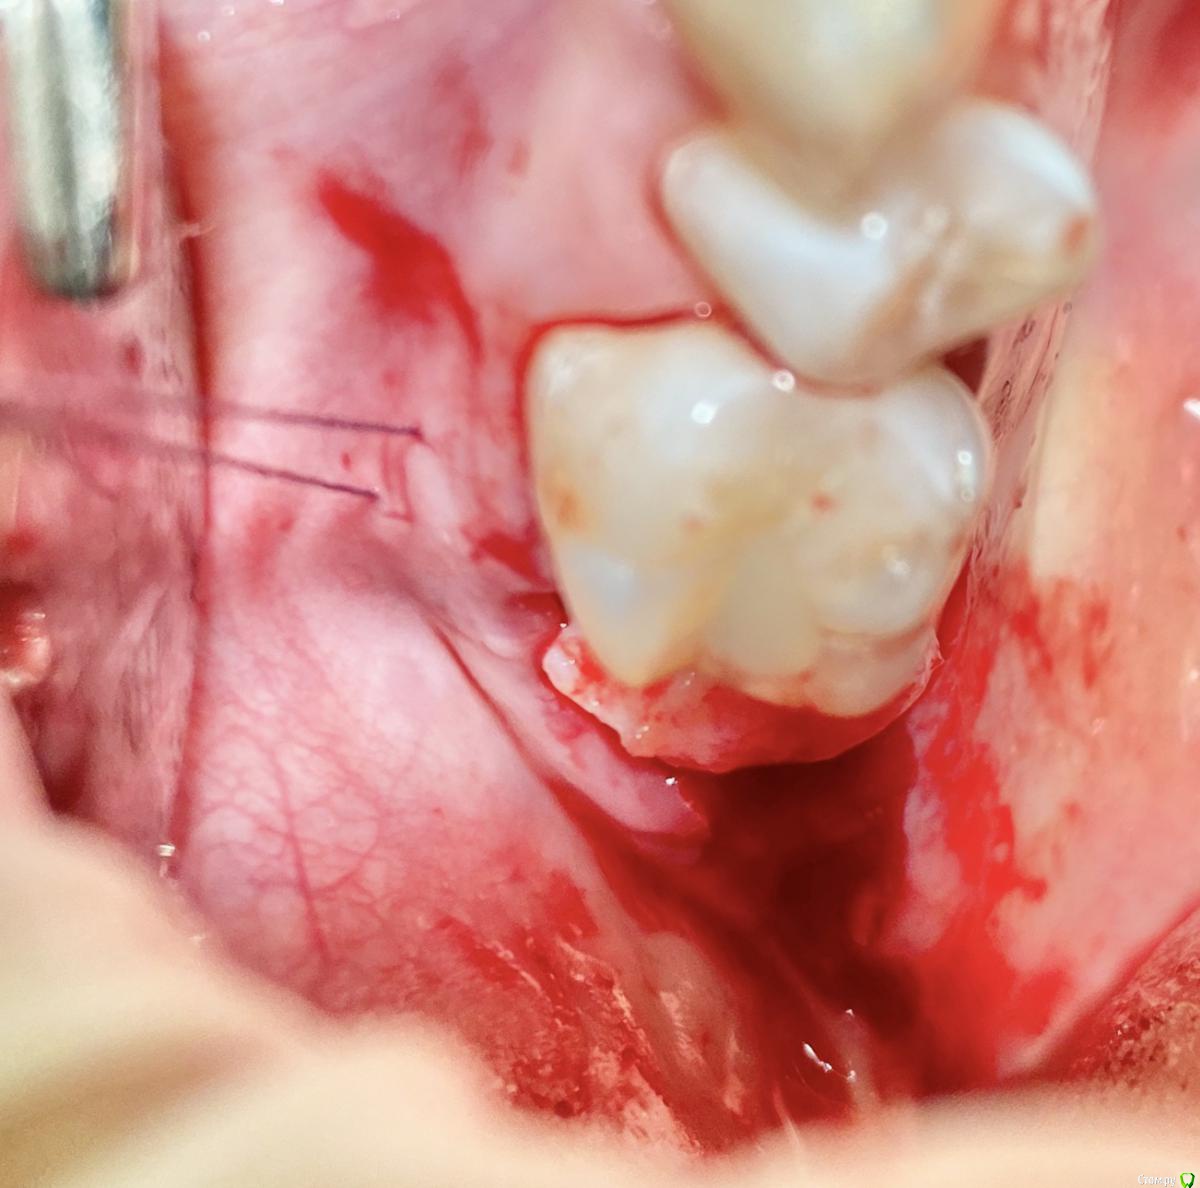

колесников Опубликовано 9 сентября, 2020 Поделиться Опубликовано 9 сентября, 2020 Т.е. на месте кривой это подслизистое отслоение, а где овал - это бугор, который нужно ротировать? овал-это бугор который мы видим и зачастую используем. Кривая-это бугор который можно забрать под слизистой. Конечно чем дальше к периферии ,тем его качество падает ,но он есть. Делаете поверхностный разрез ретромолярно,расщепляете,выделяете лоскут -заплатку,обрезаете её вестибулярно,дистально. Небно отступаете от края мм на 5 и проводите разрез до дистального края 7ки. Отделяете от основания. У вас получается заплатка на ножке. Перекидываете ее на гребень и вносите под вестибулярный край лоскута лунки,фиксируя матрасным швом. Далее придавливаете ножку перекидными швами небно-вестибулярно (ножек не прошиваем,только прижимаем). 3 Ссылка на комментарий

колесников Опубликовано 11 сентября, 2020 Поделиться Опубликовано 11 сентября, 2020 Перемещение бугра для закрытия лунки. Вестибулярно прикрепленную не смещаем. Вестибулярно компактной пластинки нет 9 Ссылка на комментарий